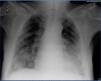

5. Chest X-ray: Bilateral interstitial and alveolar pattern with peripheral disposition and cotton-wool like distribution that does not improve following ultrafiltration (Figure 1).

Given that the patient was immunocompromised, and data supported liver failure and acute respiratory failure with skin conditions, VZV was highly probable. We decided to request a serology test for atypical cells; it was VZV-positive, so empirical treatment with acyclovir was started at a dosage of 250mg/12 hours was started, combined with antibiotic treatment (levofloxacin 250mg/48 hours plus cefotaxime 1g/24 hours). HZ diagnosis complicated with visceral dissemination was confirmed by polymerase chain reaction (PCR) for associated viral DNA, and the remaining study was negative. The patient progressed satisfactorily with acyclovir, including clinical symptoms –recovery from respiratory failure and skin lesions–, radiological symptoms, –the interstitial and alveolar infiltration disappeared– and biochemical parameters (Table 1).

Figure 1. Chest x-ray upon admission